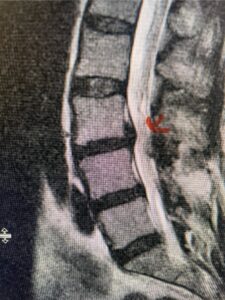

This 54-year-old morbidly obese female presents with progressive back and leg pain and quadriceps weakness. She had no diabetes. She failed all means of conservative management including physical therapy and epidural injections. On imaging she had severe stenosis at L3-4 with a disc protrusion and a slight grade 1 spondylolisthesis at L3-4 (Fig 1). We performed dynamic lumbar x-rays which demonstrated instability at L3-4 and L4-5 (Fig 2). The patient wished to have surgery. We performed an L2-4 decompressive laminectomy and L3-5 in situ fusion because of her instability. Post operatively the patient had relief of leg pain, although the patient was slow to mobilize.

Figs. 1a: Sagittal lumbar T2-weighted MRI demonstrating severe lumbar stenosis with a slight grade 1 at L3-4 and a disc protrusion (red arrow )

Fig 1b: Axial lumbar T2-weighted MRI demonstrating severe lumbar stenosis (red dot)